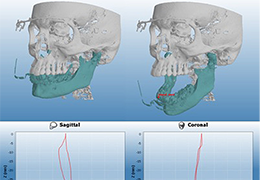

ANYTHINK 经导管主动脉瓣膜置换术分析系统